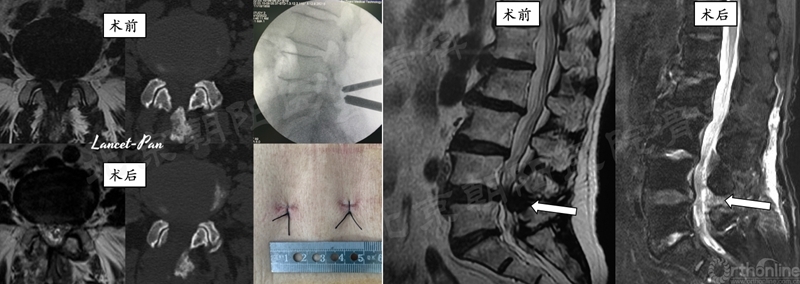

#10例UBE, L4/5 LSS。

#12例UBE,PLIF术后8年L3/4 ASD。

#9例UBE,ADS合并L4/5LDH。